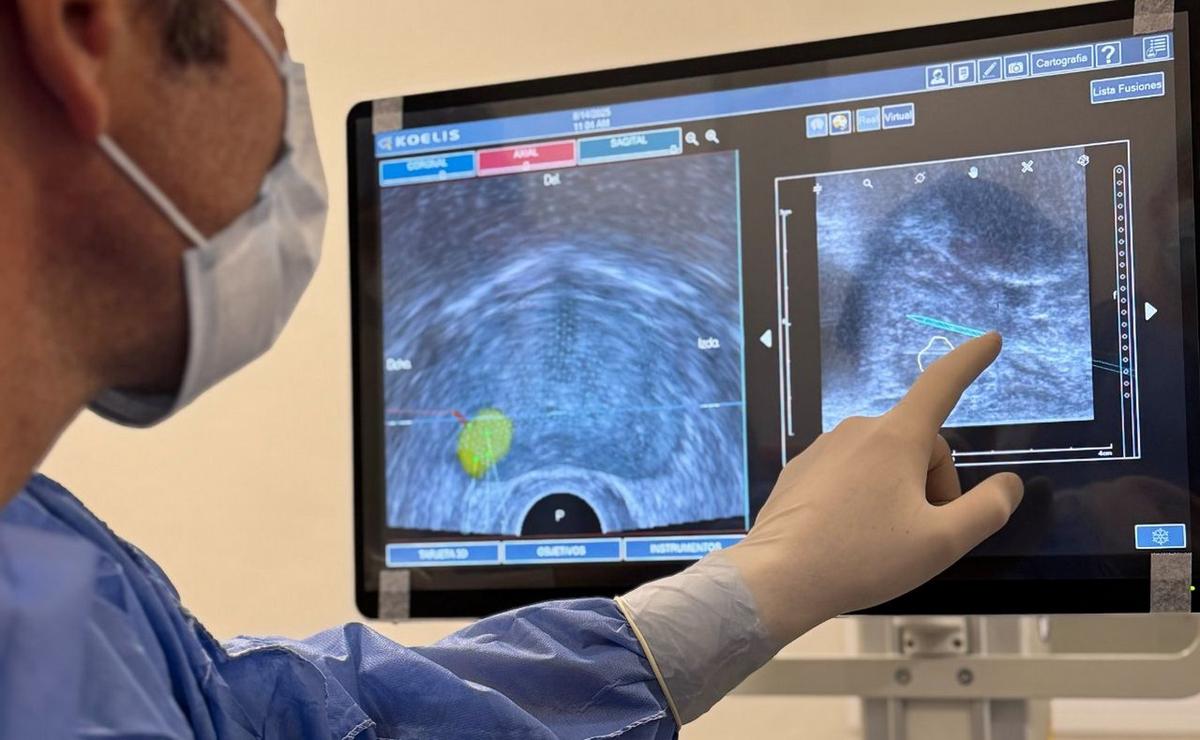

El Instituto Metropolitano de Urología (IMU) de Rosario incorporó la plataforma Koelis Trinity®, una de las más avanzadas del mundo, que permite realizar biopsias por fusión de imágenes en tiempo real. Se trata de un sistema de navegación robótica 3D, asistido por inteligencia artificial, que guía la punción hacia la lesión sospechosa detectada en la resonancia magnética con una eficacia diagnóstica superior al 90 %.

El procedimiento se realiza por vía transperineal y bajo sedoanalgesia, lo que evita el dolor y reduce al mínimo el riesgo de infecciones, una complicación frecuente en la técnica transrectal. Según explicó el urólogo Martín Piana, especialista del IMU, “es como contar con un GPS que lleva la aguja al punto exacto, en lugar de recorrer a ciegas”.

La diferencia con el método convencional es contundente: mientras la técnica clásica ofrece una eficacia diagnóstica del 45 %, la fusión de imágenes alcanza el 93 %. Esto significa que 9 de cada 10 pacientes obtienen un resultado claro en un solo procedimiento, sin necesidad de repetir estudios.